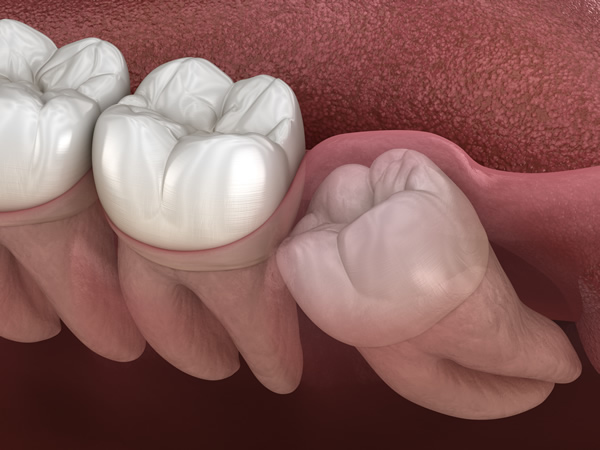

親知らずの抜歯は、その状態により難易度が大きく異なります。特に歯ぐきの中に埋まっている埋伏歯(まいふくし)の場合、通常よりも時間と技術が必要です。

「水平埋伏歯」にも対応

水平埋伏歯」とは、横向きに生えている歯のことです。この歯は手前の歯を圧迫し、痛みや歯並びの乱れを引き起こす可能性があります。また、虫歯歯周病の原因にもなります。